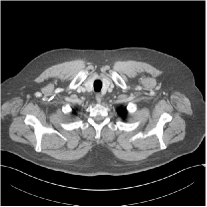

III.C. Low-dose Experiments with Mayo Clinic Data

First, we study transform training based on Mayo Clinic data. As shown in Fig. 6, seven slices obtained at regular dose from three patients are used for transform learning. The number of pixels . Similar to the phantom experiments, overlapping patches are extracted with a patch stride. The number of overall training patches is about . We set for ST, , , for MARS2, , , , , for MARS3, , , , , , , , , for MARS5, , , , , , , , , , , , , for MARS7. The iteration number in Algorithm 1. Fig. 7 illustrates the learned transforms obtained with Mayo Clinic data. Different from the XCAT phantom case, these transforms up to MARS5 display more complex features and structures. The rich features of the MARS models better sparsify the training images over layers compared to the single-layer model (ST).